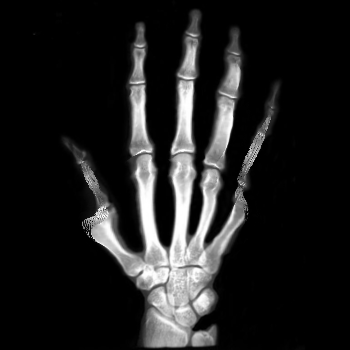

We then consider another example of registering two hand X-ray images with larger deformations (see Fig. 8(a) for the source image, Fig. 8(b) for the target image, and Fig. 8(c) for their absolute intensity difference). The warped image produced by our proposed method (Fig. 8(d)) again closely resembles the target image with the intensity difference significantly reduced (see Fig. 8(e)). Fig. 8(f) shows that the mapping is smooth and bijective. For comparison, note that LDDMM [5] fails to match the fingers (Fig. 8(g)). While DROP [18] is capable of registering the fingers (Fig. 8(h)), it distorts the boundary shape of the overall image (Fig. 8(i)).